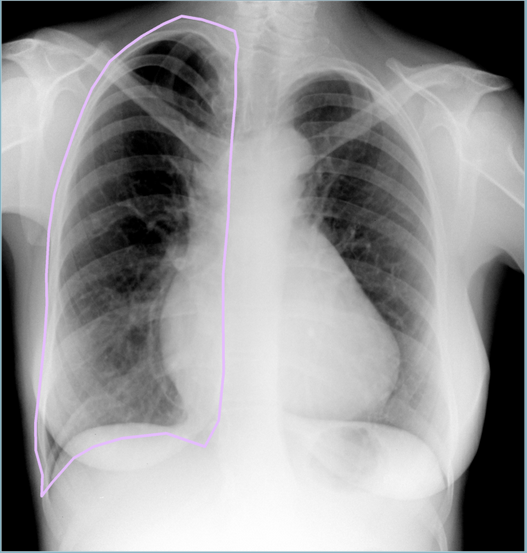

- Тесты на качество разметки. Некоторые косяки разметки вполне можно ловить автоматически. К примеру, иногда крепкая рука врачей дрожит и кликает не на тот класс объекта. На снимке снизу врач разметил перелом размером с лёгкое. Взгляд на гистограмму размеров объектов класса "Перелом" в обучающей выборке позволяет понять, что тут могла закрасться ошибка... Такие снимки можно автоматически помечать для последующего ревью.